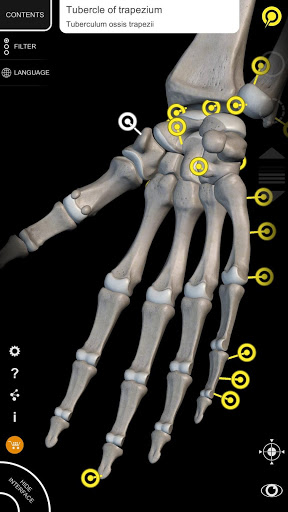

يتيح لك "Anatomy 3D Atlas" دراسة التشريح البشري بطريقة سهلة وتفاعلية.

من خلال واجهة بسيطة وبديهية، من الممكن ملاحظة كل بنية تشريحية من أي زاوية.

تتميز النماذج التشريحية ثلاثية الأبعاد بتفاصيل خاصة ودقة تصل إلى 4K.

يسهل التقسيم حسب المناطق والمناظر المحددة مسبقًا مراقبة ودراسة الأجزاء الفردية أو مجموعات الأنظمة والعلاقات بين الأعضاء المختلفة.

• من خلال تحديد نموذج أو دبوس، يظهر المصطلح التشريحي ذي الصلة